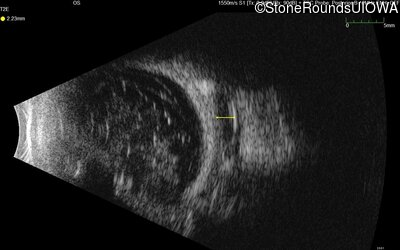

Visit at age: 37 years

B-Scan Ultrasonography - Right - Light Perception

Exemplar